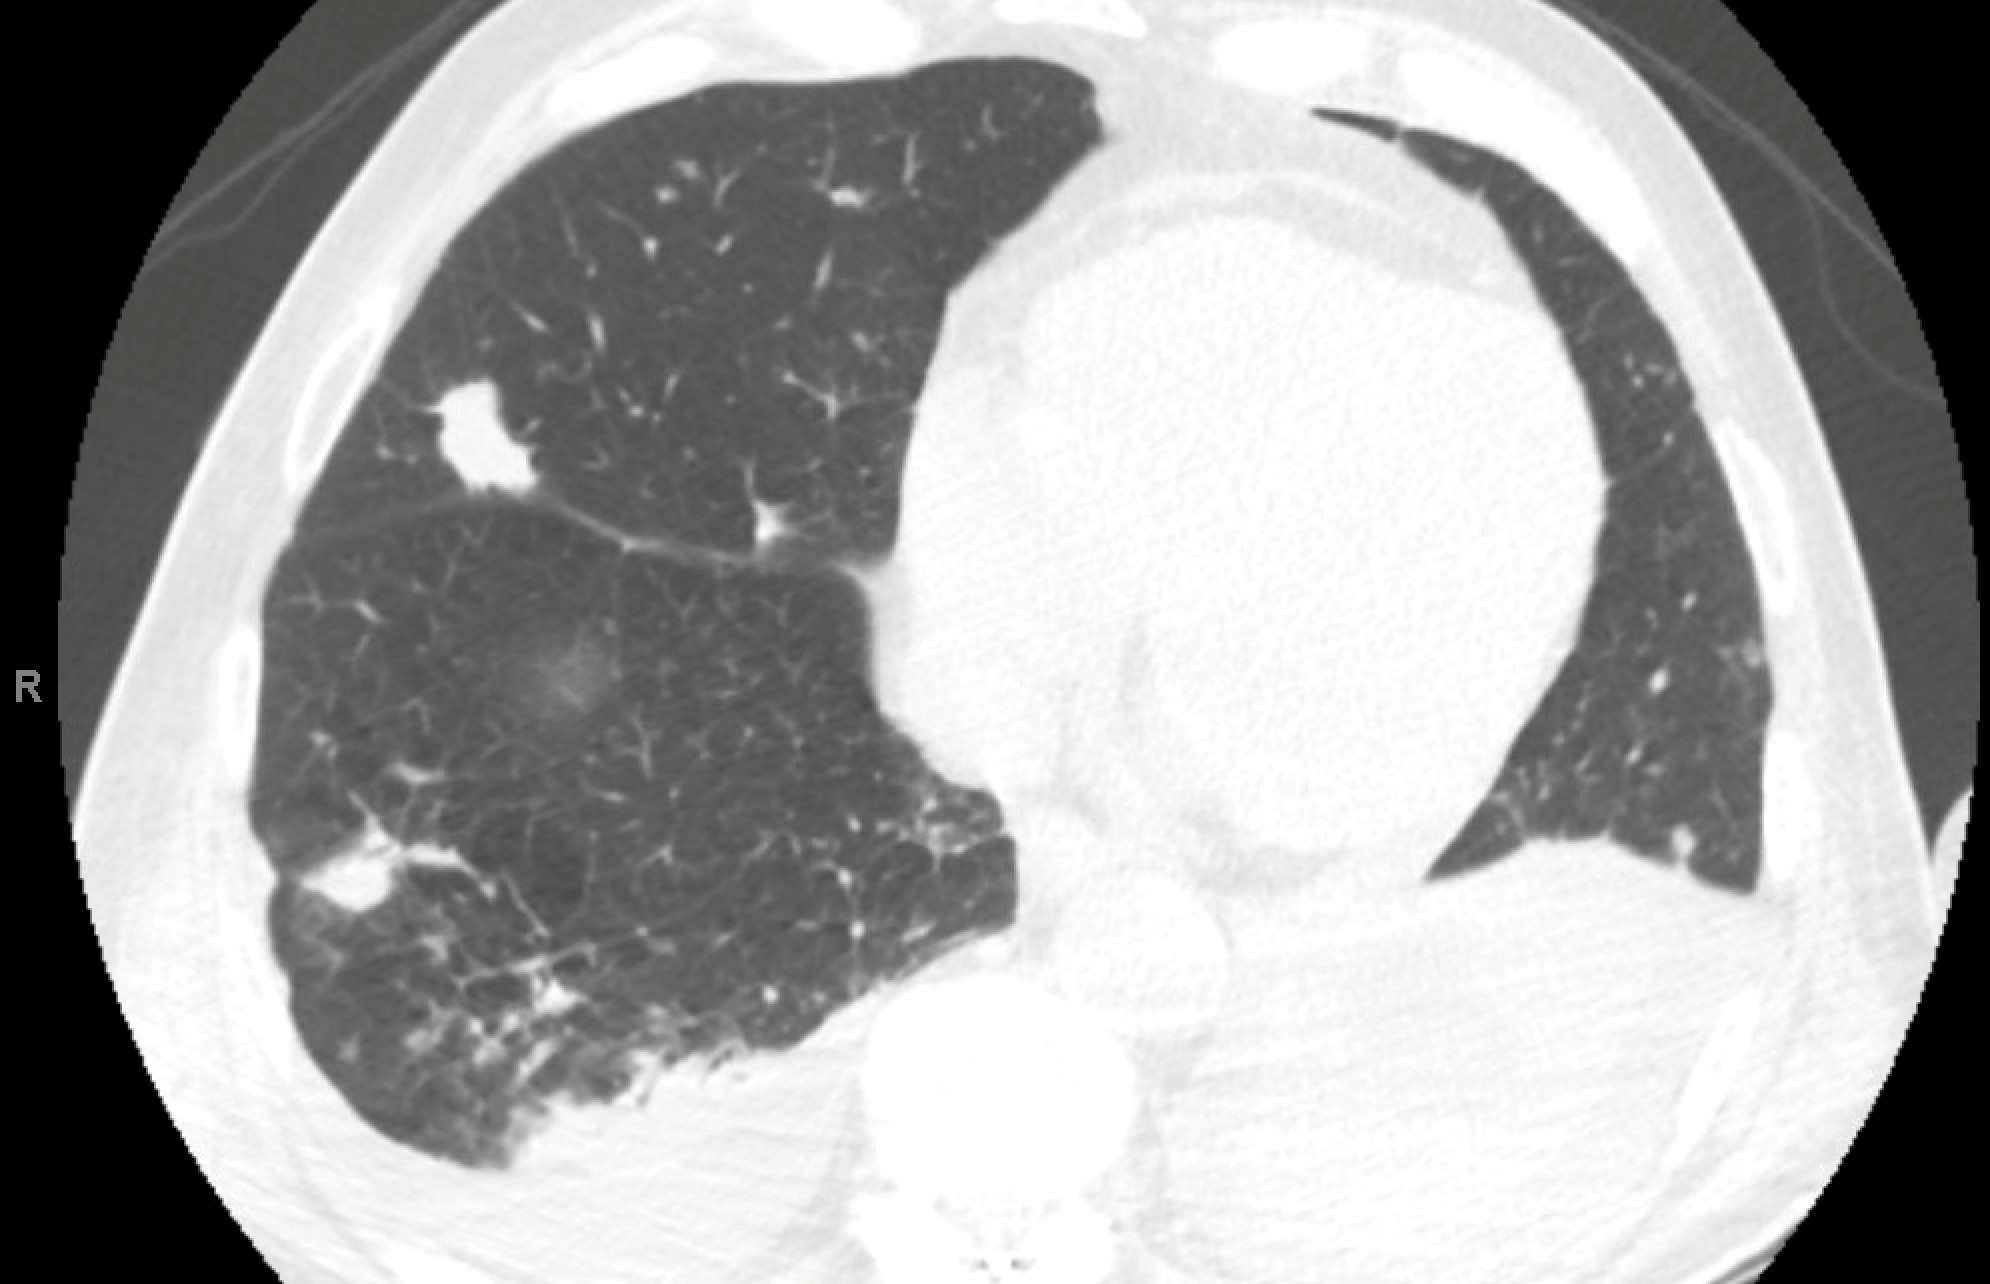

A 69-year-old man with a history of liver transplant for hepatitis C–related cirrhosis and hepatocellular carcinoma in 2010 on cyclosporine, mycophenolate, and prednisone, mantle cell lymphoma on ibrutinib, pancreatic cancer status post resection in 2009 CKD stage 4; and hypertension presents with right arm pain and swelling, dysuria, and shortness of breath requiring 3 L/min nasal cannula. He reports a two-week history of cough with difficulty expectorating and intermittent wheezing. He denies fever, chills, hemoptysis, orthopnea, lower-extremity edema, or night sweats. On exam, he is lethargic , afebrile. He is hemodynamically stable. Lungs are clear to auscultation, there is no palpable adenopathy. Right arm and elbow is markedly edematous and erythematous, with fluctuance, no crepitus, no purulence or drainage. Blood cultures are negative, and echocardiography without vegetations. Complete blood count with mild anemia and normal WBC.

The following are representative cuts of his CT chest.

Which of the following is the most plausible diagnostic consideration?

A. Septic pulmonary emboli

B. Pulmonary nocardiosis

C. Invasive aspergillosis

D. Pulmonary metastases

E. Reactivation tuberculosis